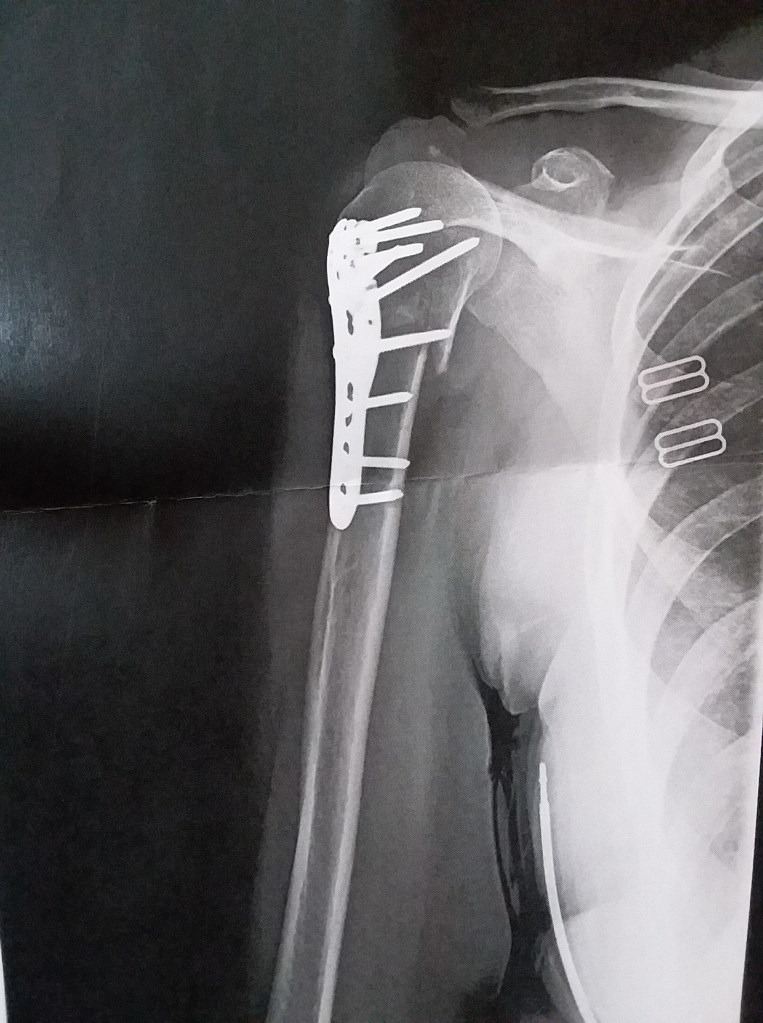

It’s been two weeks since this operation and 18 days since the break. The doctor told me today that it was just a mess inside there. More breakage then they thought, but things look good now. Still not allowed to do much but I can keep the sling off more. Still can’t use my right hand to start the car, wipe my ass, or do much, but if I plant my body just right, I can type with both hands now! Yippee!! It’s the little things.